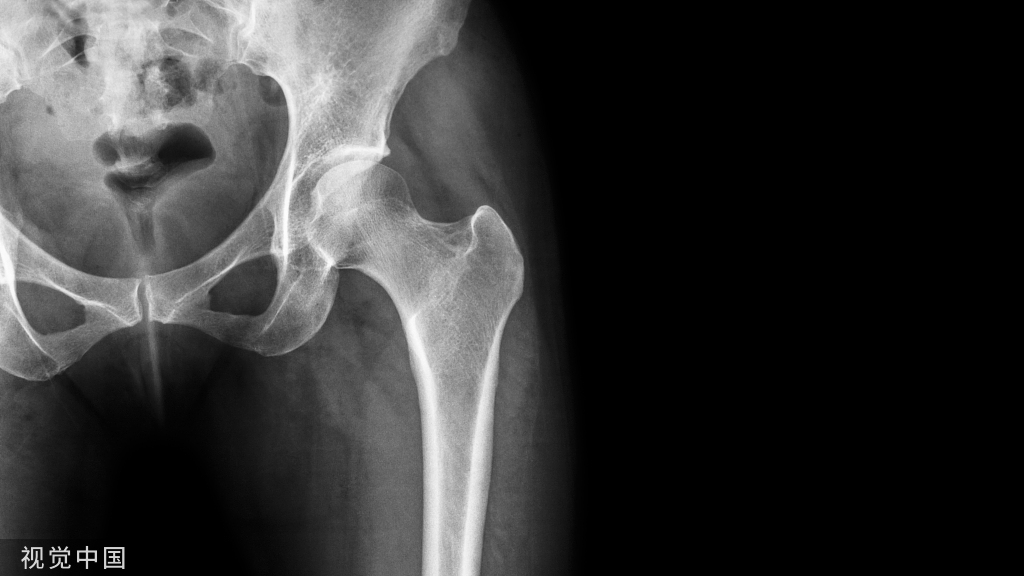

使用多孔钽假体(左髋关节)重建Paprosky IIB缺损的X线片:a)术前和b)术后10年的正位X线片。